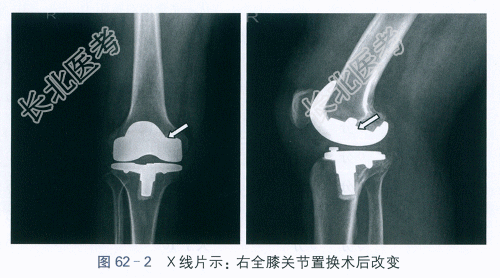

右膝关节X线片:右膝关节骨性关节炎,如图62-1所示。